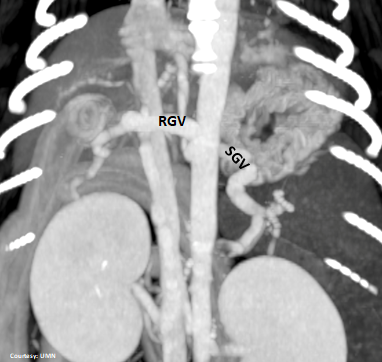

Does the RIGHT GASTRIC VEIN (RGV) contribute blood to the shunt?

Does the SHORT GASTRIC VEIN (SGV) contribute blood to the shunt?